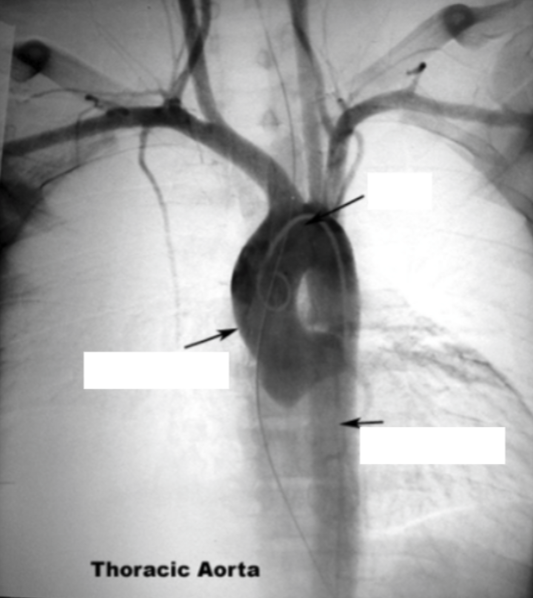

Please label the aneurism in the aortic arch